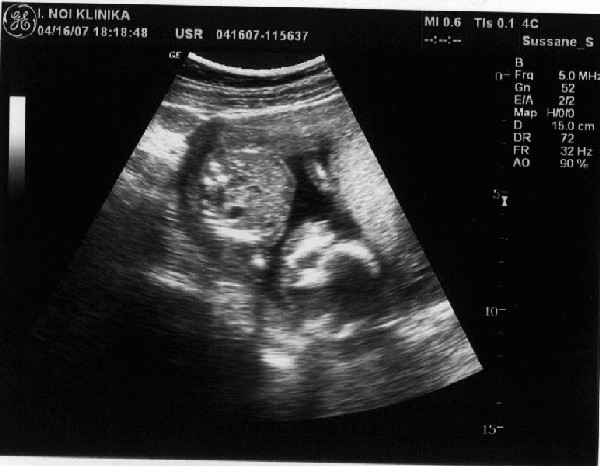

Szóval mi is voltunk genetikai UH-n és minden rendben volt. A hölgy nem volt túl kedves és semmit nem magyarázott el és kicsit gyors is lett az egész, de nem panaszkodom, mert nem lettek olyan rossz élményeim, mint egyeseknek.

Viszon a mi kis drágánk még titkolódzik egy picit, a lába közé kapta a köldökzsinórt :)

Pár kép róla:

Az első képen cumizik, remélem ti is látjátok. :) Kicsit összekeverhető melyik a feje és a pocakja, de annnyit segítek, hogy fejjel lefelé van :).